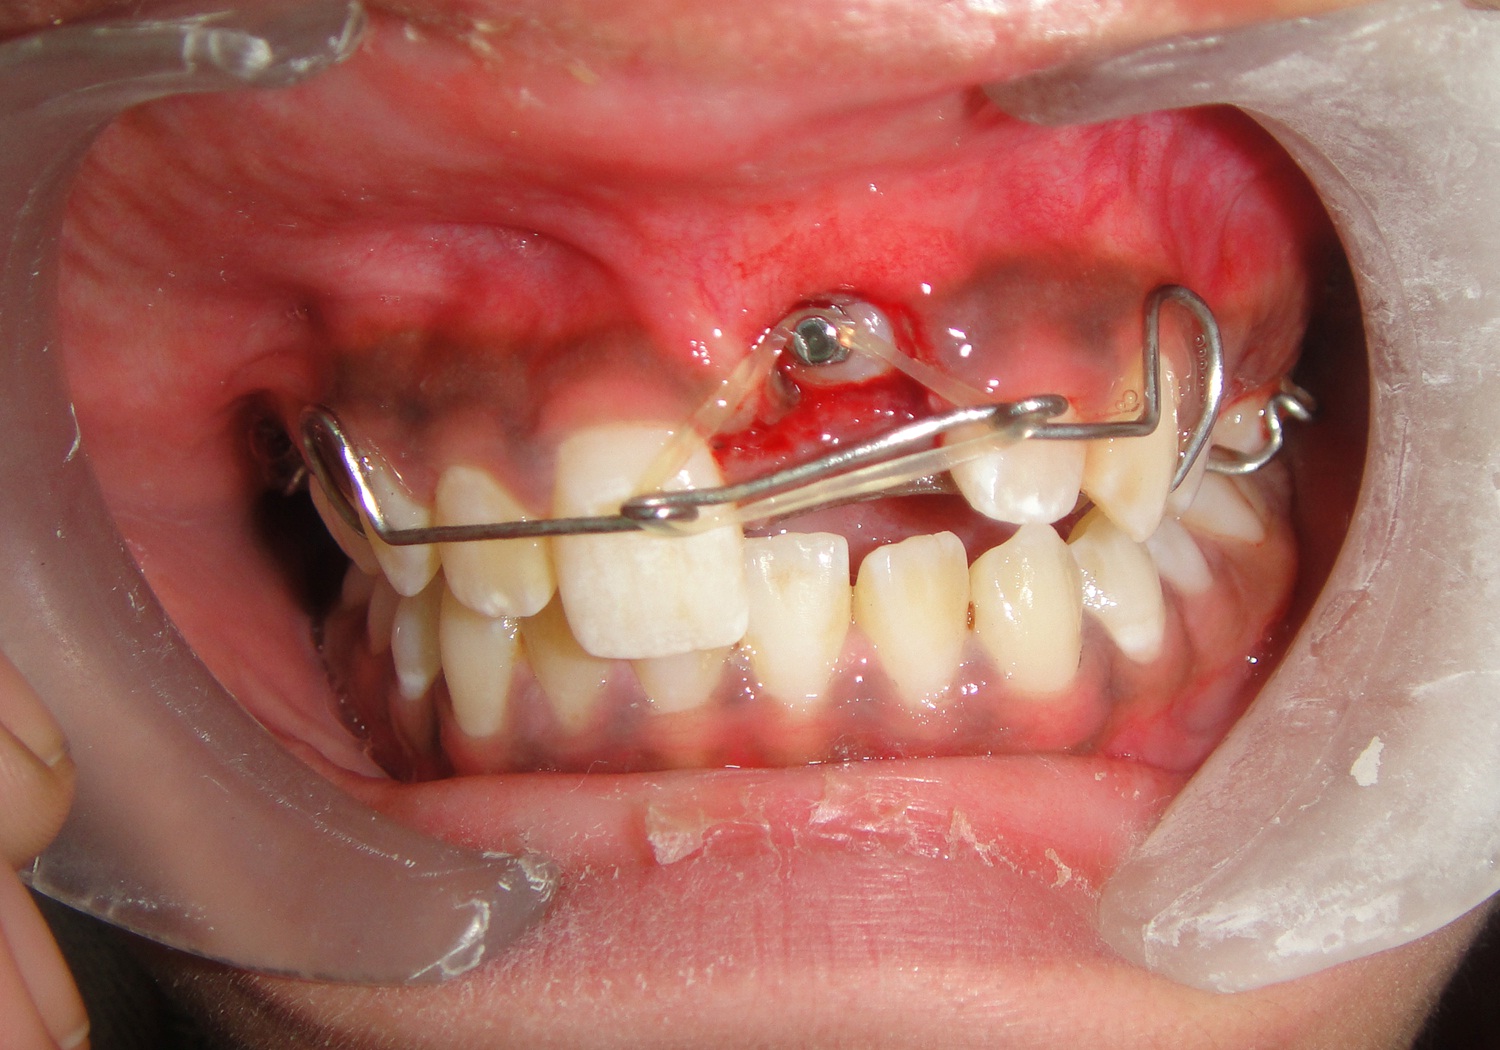

A 12-year-old female patient reported to the Department of Orthodontics of Maulana Azad Institute of Dental Sciences, New Delhi with chief complaint of missing upper front tooth. On clinical examination it was found that maxillary left central incisor (21) was missing [Table/Fig-1]. No significant history of trauma or premature/delayed shedding of primary left central incisor was reported. Panoramic and maxillary occlusal view revealed impacted left central incisor with dilacerated root [Table/Fig-2,3]. Since the contralateral central incisor had erupted fully in the mouth and the root formation of the impacted central incisor was almost complete, it was decided to disimpact the tooth (21). Disimpaction was planned by surgical exposure followed by elastic traction with the help of removable appliance. Since the patient had well aligned upper and lower arches in good occlusion, it was decided to use a modified removable appliance for extrusion of 21. A removable appliance with modified labial bow was fabricated. Labial bow in the anterior region was fabricated with 22 gauge wire and helices were incorporated in the labial bow adjacent to left central incisor region. Retention was provided by the acrylic coverage in the palatal region and by well formed retentive clasps. Surgical exposure of left central incisor was performed by open exposure technique. A bondable button was placed onto the labial surface of exposed left central incisor crown [Table/Fig-4]. Patient was trained to use elastic in triangular fashion to engage button on 21, and two helices of the labial bow, which resulted in an extrusive force of 20 grams for disimpaction of 21[Table/Fig-5] [1]. Patient was advised to change the elastic daily and was reviewed every three weeks. At the end of six months, complete disimpaction of 21 was achieved with the tooth in its optimal alignment into the upper dental arch and in good relation with lower teeth [Table/Fig-6,7]. Post disimpaction panoramic view reveals tooth 21 in the optimal position with respect to maxillary occlusal plane [Table/Fig-8].

Intraoral frontal photograph showing mechanics for extrusion of 21 with elastic traction force.